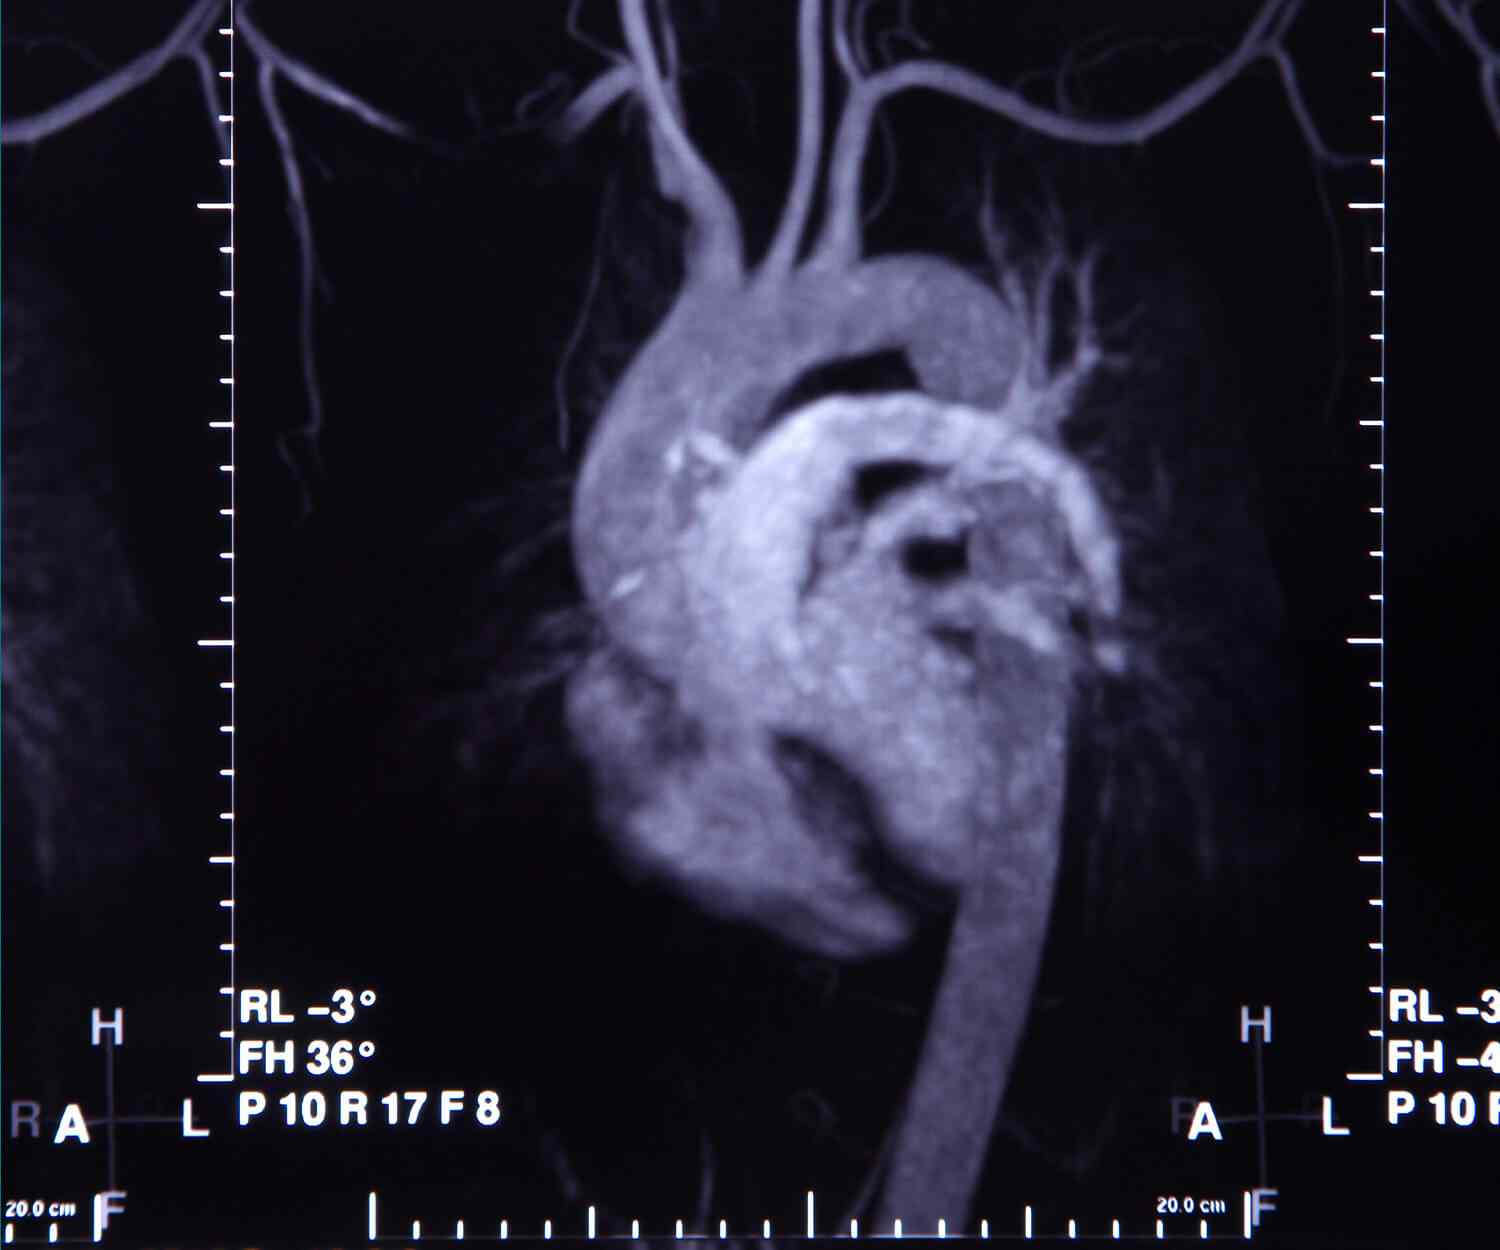

Cardiomyopathy refers to conditions that affect your heart muscle. If you have cardiomyopathy, your heart can’t efficiently pump blood to the rest of your body. As a result, you may experience fatigue, shortness of breath or heart palpitations. Cardiomyopathy gets worse over time.

There are many different types of cardiomyopathy caused by a range of factors, from coronary heart disease to certain drugs. These can all lead to an irregular heartbeat, heart failure, a heart valve problem, or other complications.

In this type of cardiomyopathy, the pumping ability of your heart’s main pumping chamber — the left ventricle — becomes enlarged (dilated) and can’t effectively pump blood out of the heart.

This type involves abnormal thickening of your heart muscle, which makes it harder for the heart to work. It mostly affects the muscle of your heart’s main pumping chamber (left ventricle).